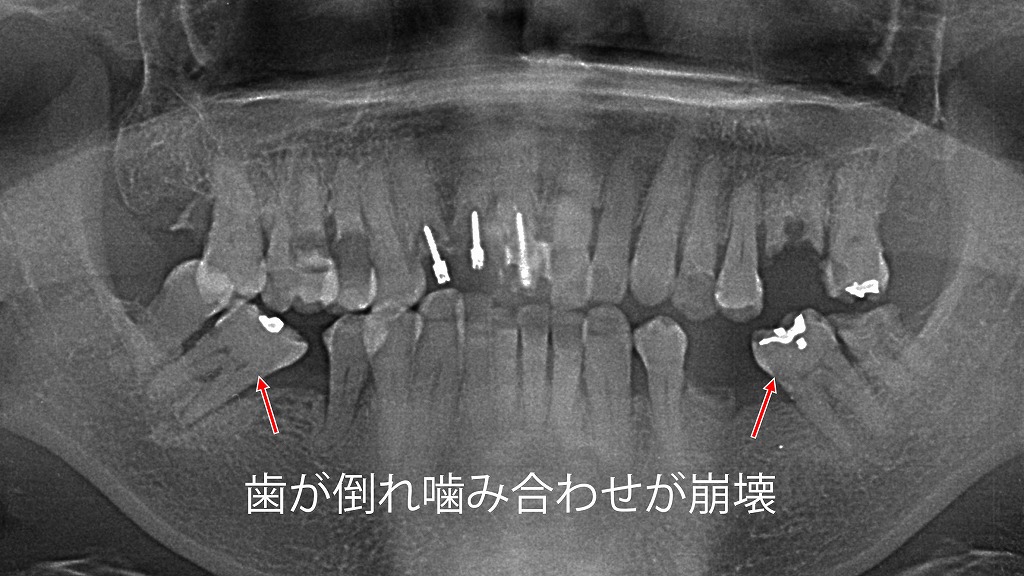

さらに、歯を失ったまま放置すると、隣の歯が欠損部へ倒れ込み、対合歯が伸び出して咬合崩壊を引き起こします。

奥歯の虫歯による「歯の傾斜」と咬合崩壊

奥歯の虫歯を放置すると、歯が欠損・機能低下し、隣の歯が空いたスペースに倒れ込んできます。その結果、噛み合わせ全体のバランスが崩れ、反対側の歯や顎関節にも過剰な負担がかかります。噛みにくさや顎の痛み、さらなる虫歯・歯周病の連鎖を防ぐためにも、奥歯の虫歯は早期治療が重要です。